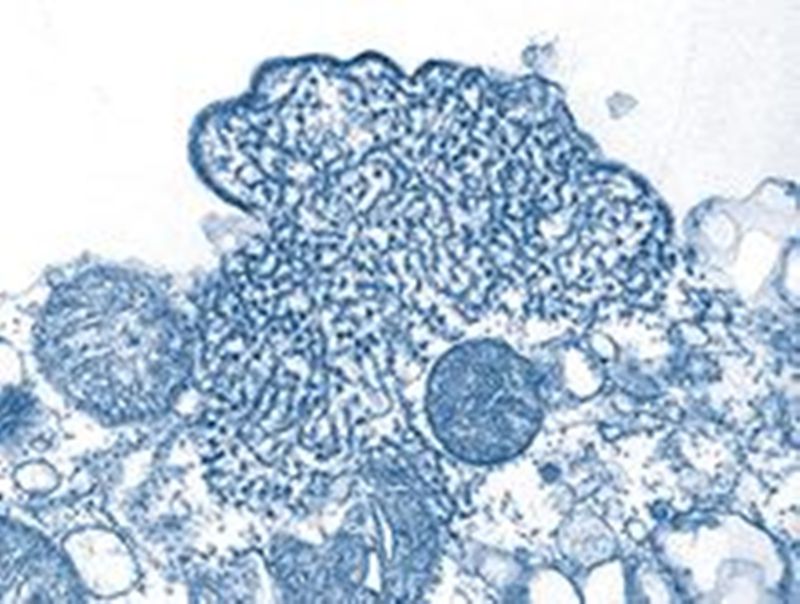

Nipah VIrus